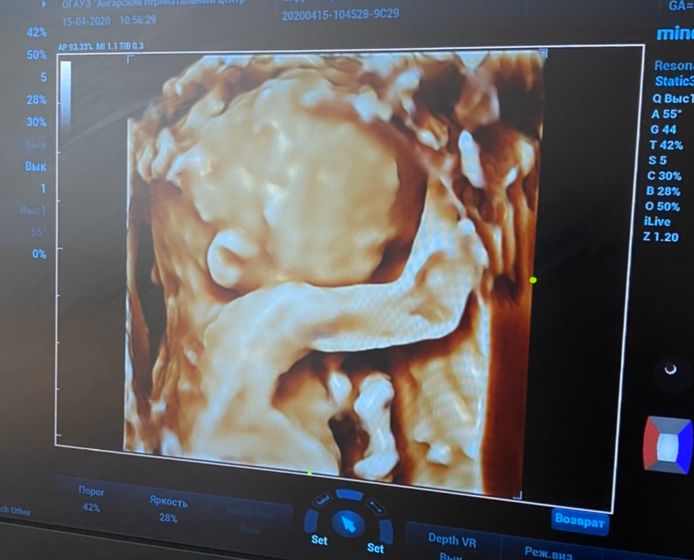

Сегодня были на 2 скрининге, срок 19,6. С малышом всё хорошо, здоров. Мальчик☺️ единственное, в заключении написали — ГЭФ ЛЖ 1,6. Девочки, кто-нибудь сталкивался? Не стоит волноваться?

Рассосалось к 3 скринингу, было 2 ГЭФа

Меня врач успокоил, сказал это не диагноз, не обращай внимания

На третьем скрининге повнимательнее сердечко посмотреть попросите.